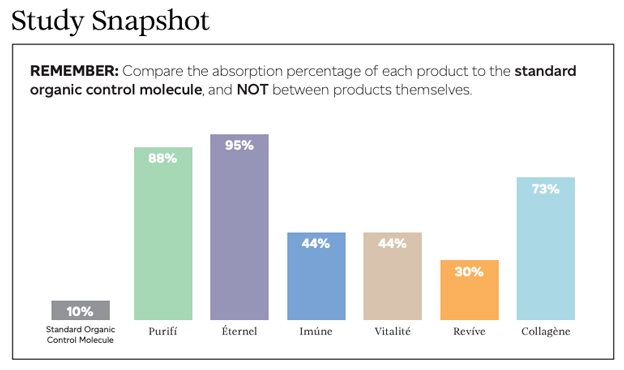

Predicted cellular absorption and bioavailability percentages of THREE’s products are shown in Figure 1 below. Actual numbers are as follows: Éternel = 95%, Purifí = 88%, Collagène = 73%, Vitalité = 44%, Imúne = 44%, Revíve = 30%, and curcumin (Organic Control) = 10.

The correct way to analyze the data in Figure 1 is to compare the percent absorption of each product to the organic control—and not between products.

When looked in this way, Revíve, with a cellular absorption percentage of 30, is 3X more bioavailable than curcumin (organic control), which represents a standard organic molecule and served as the control in the experiment. Éternel is 9.5X more bioavailable than curcumin. The significant increases in cellular absorption and bioavailability in THREE’s products versus a standard molecule like curcumin (organic control) is due to the Cellular Absorption Technologies used in THREE’s products that help to shuttle the ingredients in the formulas across the cellular membrane and into the cell at a much higher concentration.

The data found that THREE’s products, due to the Cellular Absorption Technologies used, are between 3 and 9.5 times more absorbable than a standard organic molecule using no delivery technology. Increased cellular absorption and bioavailability should equate to increased product efficacy.

The purpose of this clinical study was to determine the cellular absorption and bioavailability of THREE’s product line, meaning, at what percentage are the nutrients included in THREE’s product line being absorbed by the body?

The results of this study indicate that due to the Cellular Absorption Technologies used in formulation and manufacturing, THREE’s products are between 3 and 9.5 times more absorbable than the standard organic control molecule used as a baseline in the study.